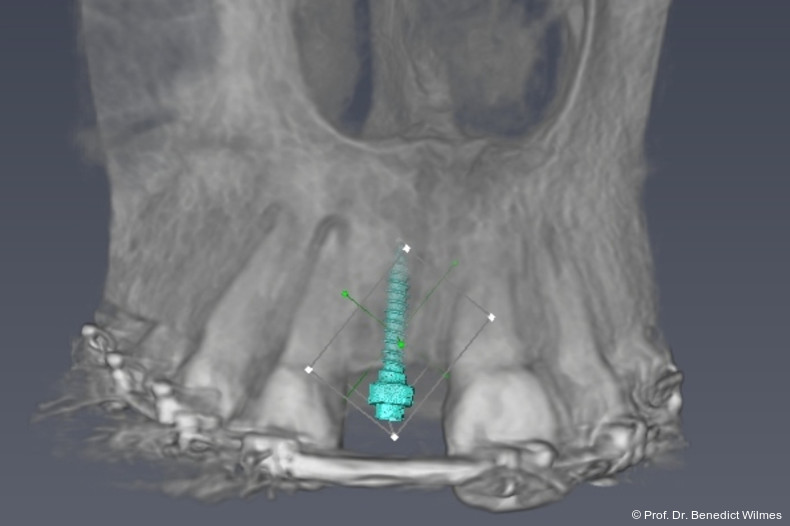

Die temporäre Versorgung eines fehlenden Oberkieferfrontzahnes beim Jugendlichen mit einem Miniimplantat stellt sich als eine sehr empfehlenswerte Therapiealternative zu Klebebrücke und Prothese dar. Die Ziele einer ästhetisch ansprechenden Interimsversorgung sowie eines Knochenerhalts können sehr gut mit dieser Methode erreicht werden. Dank neuer CAD/CAM-Techniken können die „Kinderimplantate“ heutzutage auch mit einem Insertionsguide nach dreidimensionaler Planung eingesetzt werden (Abb. 17–19).